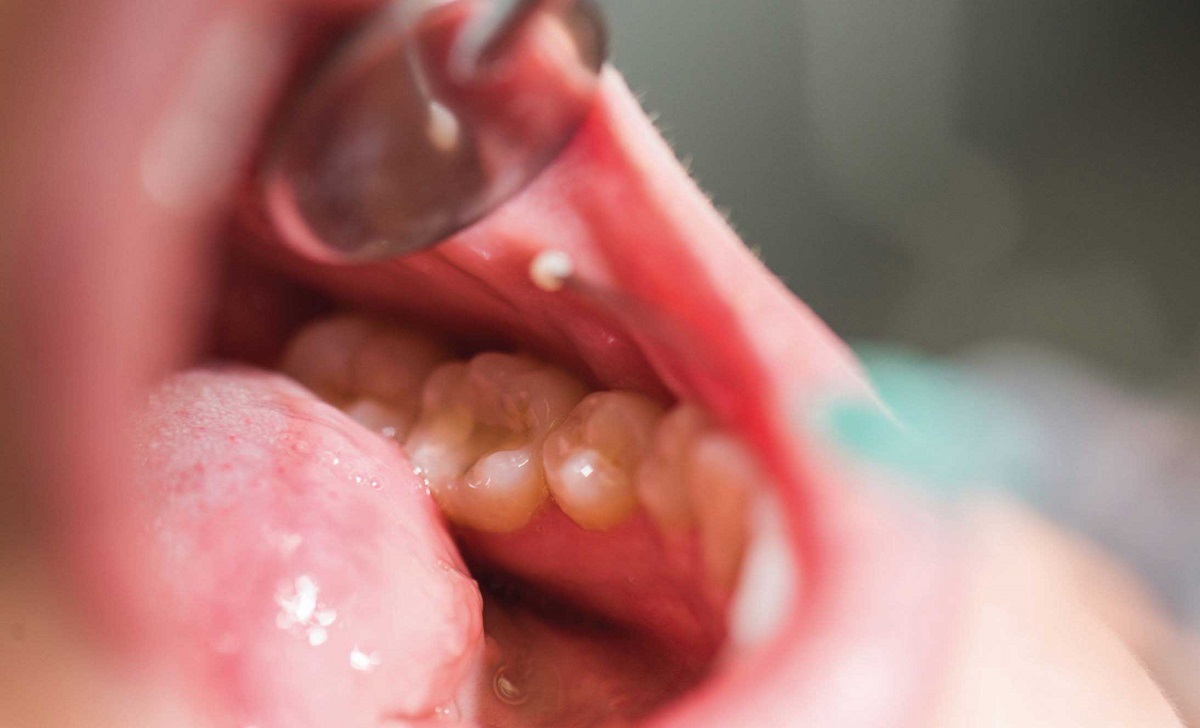

زخمهای دهانی که بهبود نمییابند: یکی از شایعترین علائم سرطان دهان، بروز زخمهایی است که بیشتر از دو هفته در دهان یا روی لثهها باقی میمانند و بهبود پیدا نمیکنند.

تورم یا توده در دهان یا گردن: در برخی موارد، تودههای غیرطبیعی در لثهها، زبان یا داخل گونهها ممکن است قابل مشاهده باشند. همچنین تورم غدد لنفاوی در گردن نیز میتواند نشانهای از وجود سرطان باشد.